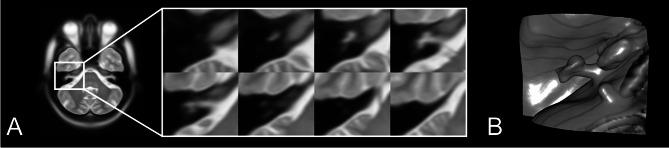

优化多受试者内耳磁共振成像的空间归一化:不同几何保留配准方法的比较

Optimizing spatial normalization of multisubject inner ear MRI: comparison of different geometry-preserving co-registration approaches.

Spatial normalization of multisubject inner ear imaging data is challenging, due to both substantial intraindividual differences and the small size of the organ compared to other intracranial structures. Automatic whole brain co-registration to standard space can only roughly co-align the peripheral vestibular endorgan, and complemental manual registration is highly time-consuming. Here, we compared the accuracy of four geometry-maintaining co-registration methods (one semi-manual method and three automatic methods). High-resolution structural T2-MRI of 153 inner ears from patients and healthy participants were co-registered to an inner-ear atlas. The semi-manual method used a three-point landmark-based approach (3P), two automatic methods were based on unassisted standard algorithms (Advanced Normalization Tools (ANTs), Elastix (EL)), while the fourth automatic method utilized a volumetrically dilated, atlas-based mask (thick inner ear, TIE) for probabilistic inner ear masking. Registration accuracy was evaluated by neurotologists blinded to the respective registration paradigm, and the resulting median volumes were quantified using colocalization analyses. The mask-aided automatic approach showed the best ratings, followed by the semi-manual three-point landmark-based registration (mean ratings (lower: better) TIE 2.21 ± 1.15; 3P 2.58 ± 0.61; EL 3.42 ± 1.06; ANTs 3.49 ± 1.26). The semi-manual method had the lowest rate of insufficient registrations, followed by TIE (3P: 3.70%; TIE: 8.28%; EL: 22.66%; ANTs: 27.02%). TIE showed the highest colocalization metrics with the atlas. Only TIE and 3P allowed for sufficient semicircular canal visualization in method-wise average volumes. Overall, geometry-preserving spatial normalization of multisubject inner ear imaging data is possible and could allow groupwise examinations of the bony labyrinth or temporal bone morphology in the future.

摘要